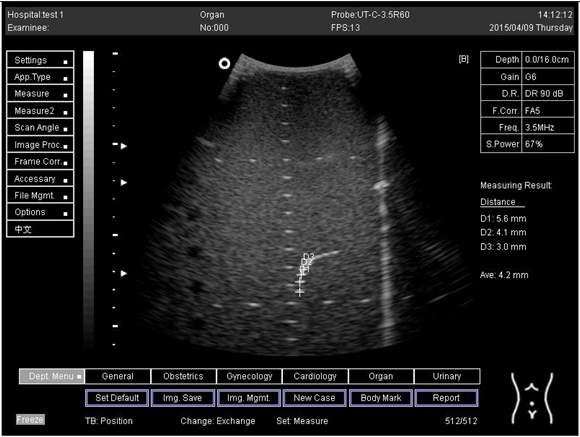

16.0Axial resolution

Biomimetics 07 00130 i025

D1 = 5.6

D2 = 4.1

D3 = 3.0

Lateral resolution

Biomimetics 07 00130 i026

D1 = 5.0